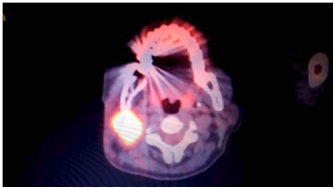

A 60 year old female was presented to the Otolaryngology Department at Hammoud Hospital University Medical Center for right neck mass. The patient was known to have diabetes type 2, hypertension and coronary artery disease status post open heart surgery. The mass was at the site of the parotid gland, painless, firm, rubbery, and non-mobile. Computerized tomography scan (CT scan) of the neck with intravenous contrast was ordered and done. It revealed presence of enlarged right parotid gland with irregular borders and locally enlarged lymph nodes suggestive of malignancy (Figure 1). A total body positron emission topography scan was done afterwards and revealed a malignant picture of the right parotid gland and the surrounding lymphatic structures. Right total parotidectomy with lymph node dissection was scheduled (Figure 2).

Figure 2 PET scan of our patient showing primary malignant salivary gland tumor with local and distant metastasis.